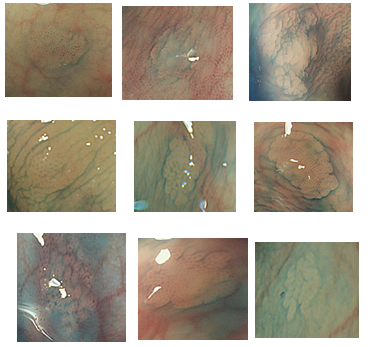

この理由は3つあります。過形成ポリープ・SSAPは(1)見落とし易く(2)境界が不明瞭なため切除が不完全になり易く(3)急激に癌化することがあるのです。

SPS症候群は「見逃されることが多い」という実態もあります。特に「軽症型のSPS症候群(=MSP症候群)」は診断が付かないまま放置されている場合も多いです。(詳しく・・・)